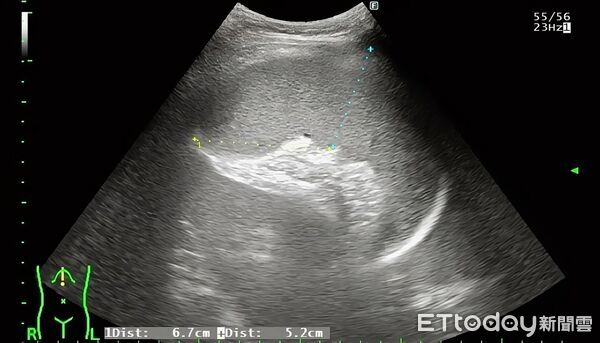

▲男童腹部超音波顯示肝臟與脾臟異常腫大。(圖/張靖醫師授權提供)

由於男童腹脹,張靖先進行腹部超音波,沒想到發現肝臟與脾臟異常腫大,他錯愕地說,「當時的我根本不知道弟弟到底發生什麼事,是特殊病毒感染嗎?還是血液科問題?」只知道真的須轉診至醫學中心了。